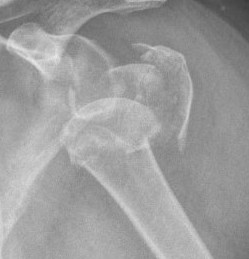

Three part

Three part with greater tuberosity fracture

Three part fracture dislocation anterior

Three part fracture dislocation with anatomical neck

Three part head splitting fracture